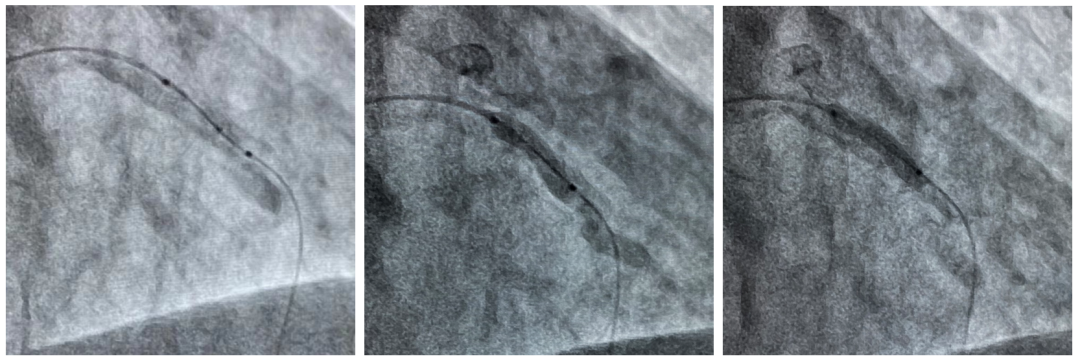

导管支持下通过Shockwave球囊(左)

初始Shockwave不能完全膨胀(中)

冲击治疗后Shockwave球囊完全膨胀(右)

延长导管支持下,3.0mmx12mm Shockwave冲击波球囊精准定位于前降支近段钙化最重处,先后触发60次脉冲冲击波(6个周期),实施钙化斑块碎裂术,对治疗段进行低压球囊扩张成形,随后通过OCT及冠脉造影融合技术证实,部分钙化病变得到松解,但中段成角病变处OCT提示仍有严重偏心钙化斑块,再次进行了20次脉冲冲击波(2个周期)治疗后,随着shockwave球囊能量的逐步释放,再次复查OCT显示原钙化环断裂,深层钙化碎裂。经过充分的冲击波球囊预处理,顺利完成进一步介入治疗。用时约40分钟,在患者无明显不适的情况下顺利完成介入治疗。术后患者顺利转入病房,并计划于近日出院。